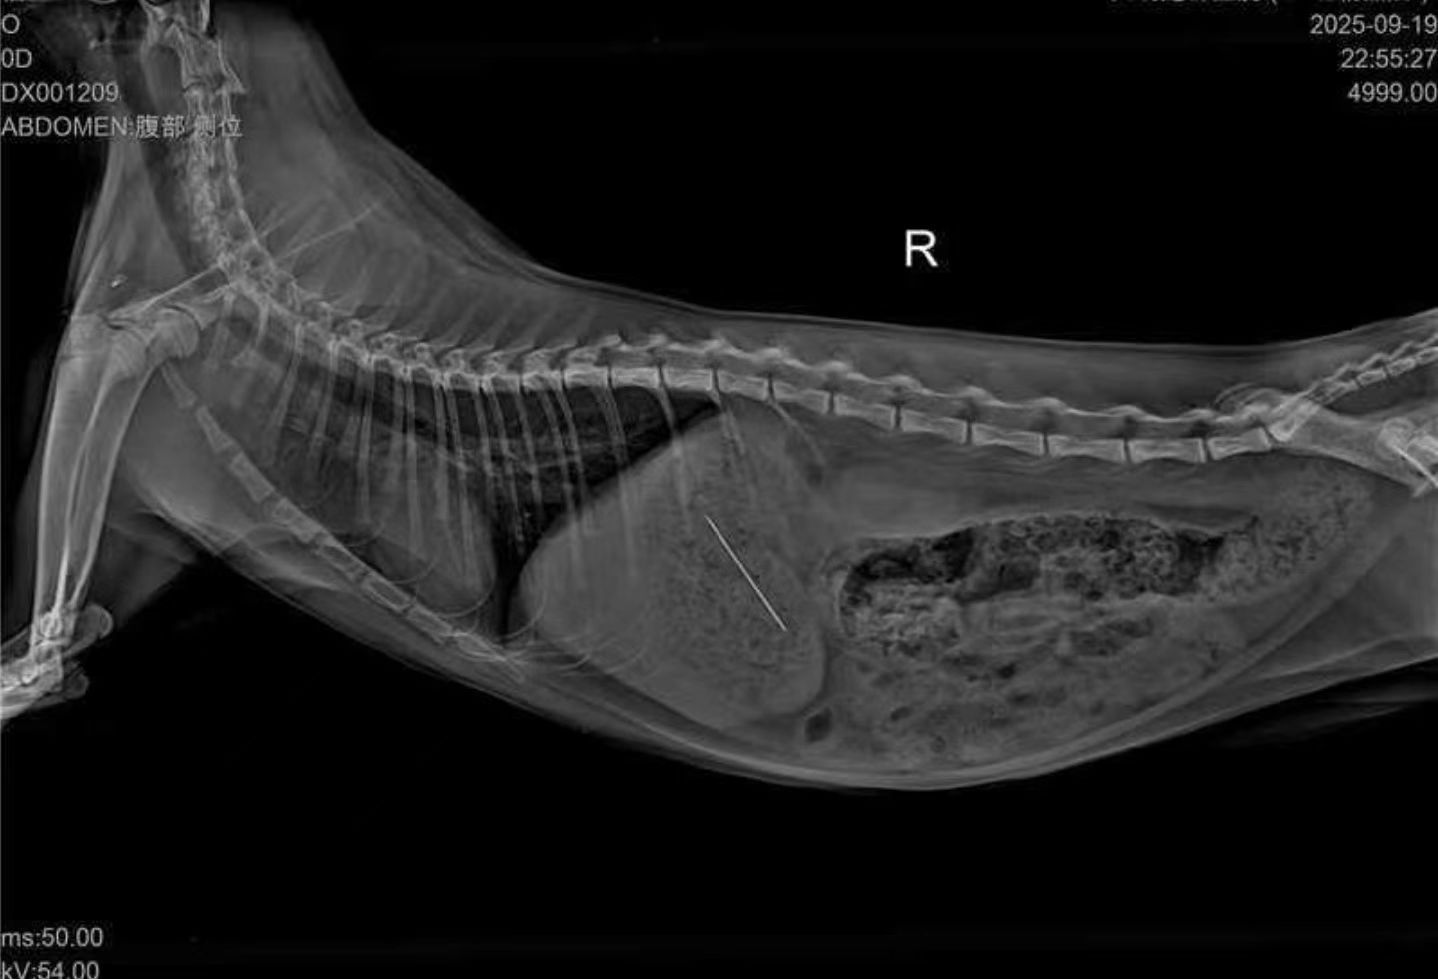

After admission, the veterinarian combined the history of “air chewing followed by swallowing a suspicious object” and strongly suspected ingestion of a high-density foreign body such as metal or plastic—materials that can easily cause gastric perforation or obstruction. Initial imaging was performed to screen for risks. The results showed an abnormal high-density shadow in the stomach, indicating the presence of a suspected foreign body that required further verification.

A JeetVet endoscope was then used for direct gastric examination. Through the high-definition camera, the veterinarian clearly observed a high-density foreign body located in the mid-stomach (consistent with the imaging findings). The surrounding gastric mucosa showed no bleeding or signs of perforation. Although no severe damage had occurred yet, the object needed to be removed promptly.